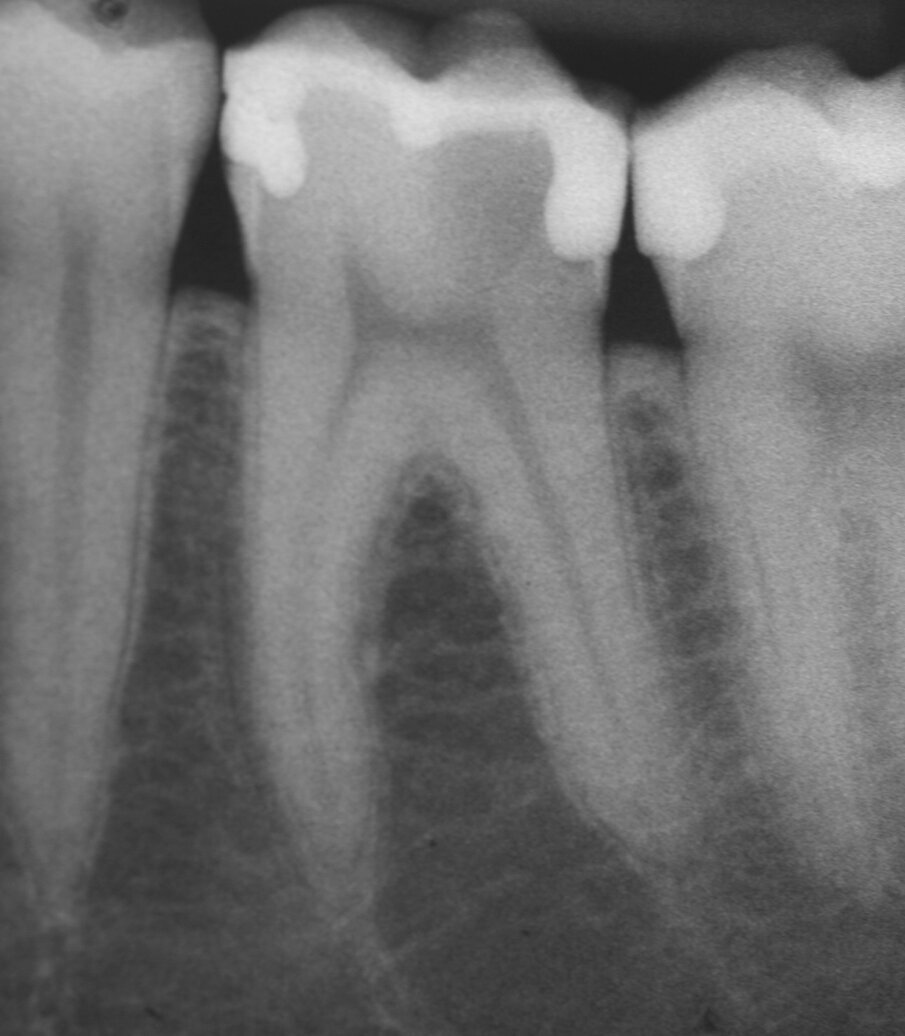

Chirurgia apicale

MTA è il materiale che vanta i migliori risultati come materiale da otturazione per la chirurgia apicale. L’MTA è stato associato ad una minore infiammazione, a formazione di nuovo cemento e alla rigenerazione del tessuto periradicolare (Torabinejad e Chivian 1999) (Figg. 4a-4f).